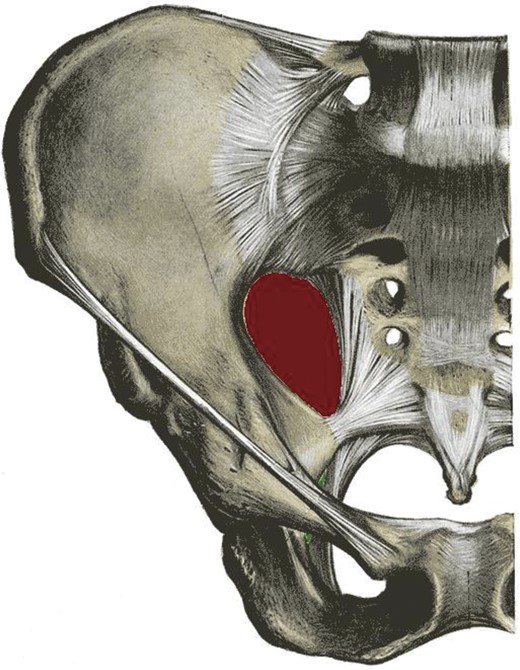

Pelvis demonstrating the greater (red) and lesser (green) sciatic foraminae.

Sciatic hernias are one of the rarest types of hernia and often pose diagnostic difficulty to the clinician [1]. A sciatic hernia is defined as herniation of intraperitoneal contents through either the greater or lesser sciatic foraminae (Fig. 3). The majority of sciatic hernias are found in women (77%) with more than one-third of these being aged 60 or over [1]. The contents are variable and hernias containing ovaries, ureters, bladder, small and large intestine, omentum and dermoid cysts have been reported [1–6]. The wide variability in contents leads in turn to a range of presentations. Cases have been reported with both acute and chronic symptom duration [2–5]. Half of patients report non-specific abdominal or pelvic pain and one third have a mass on clinical examination [1]. Sciatica, intestinal obstruction, urinary sepsis and hydronephrosis have also been described [1–5]. Diagnostic laparoscopy or laparotomy is often required to fully evaluate the sac contents and to repair the defect [2, 3, 5]. In symptomatic patients, surgical repair is indicated due to the high risk of bowel strangulation [1, 3].